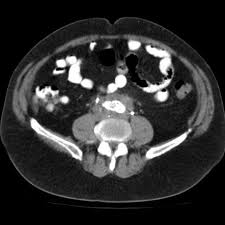

March 20, 2023When too much fibrous tissue grows in the retroperitoneal area, which is the region between the stomach and intestines, it results in retroperitoneal fibrosis, also known as Ormond’s disease. The major artery that carries blood from the heart to the regions below the kidneys is called the abdominal aorta. Although, it frequently appears between ages 40 and 60, retroperitoneal fibrosis typically affects adults rather than youngsters. Moreover, it affects men more frequently than women.

Diagnosis for Retroperitoneal Fibrosis can be done through renal function tests, liver function tests and biopsy.